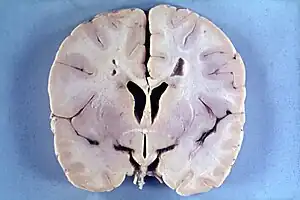

| Brain of a 4-year-old boy with Alexander disease showing macroencephaly and periventricular leukomalacia (note brownish discoloration around the cerebral ventricles) | |